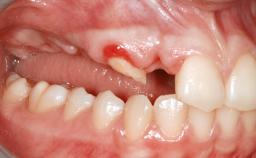

A 47-year-old woman who had suffered from aggressive periodontitis requiring a number of periodontal interventions over more than 10 years was referred by her general dental practitioner and periodontologist for bone augmentation and implant therapy. Her failing dentition had already been scheduled for extraction. The patient expressed a desire for implant-supported fixed restorations and esthetic improvement of her lower face. She had agreed to consult with a maxillofacial surgeon after the referring dentist had suggested bone augmentation. An initial examination by the maxillofacial surgeon revealed mobility of all residual teeth in a patient who was very unhappy with the function of her removable partial dentures. Due to periodontally migrated flaring teeth and loss of occlusal support, the vertical dimension of occlusion was dramatically reduced. The patient was displeased with her lower face because of deepened nasolabial, commissural, and supramental folds.

Bone Augmentation Horizontal|Sinus Floor Elevation|Staged|Vertical

Augmentation Materials Autogenous chips|Autogenous block(s)|Xenogenous|Membrane